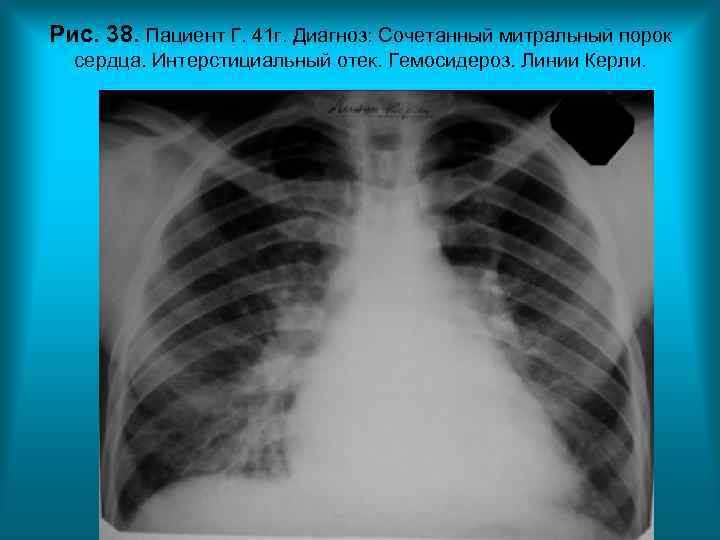

Рис. 38. Пациент Г. 41 г. Диагноз: Сочетанный митральный порок сердца. Интерстициальный отек. Гемосидероз. Линии Керли. Н. С. Воротынцева. С. С. Гольев Рентгенопульмонология